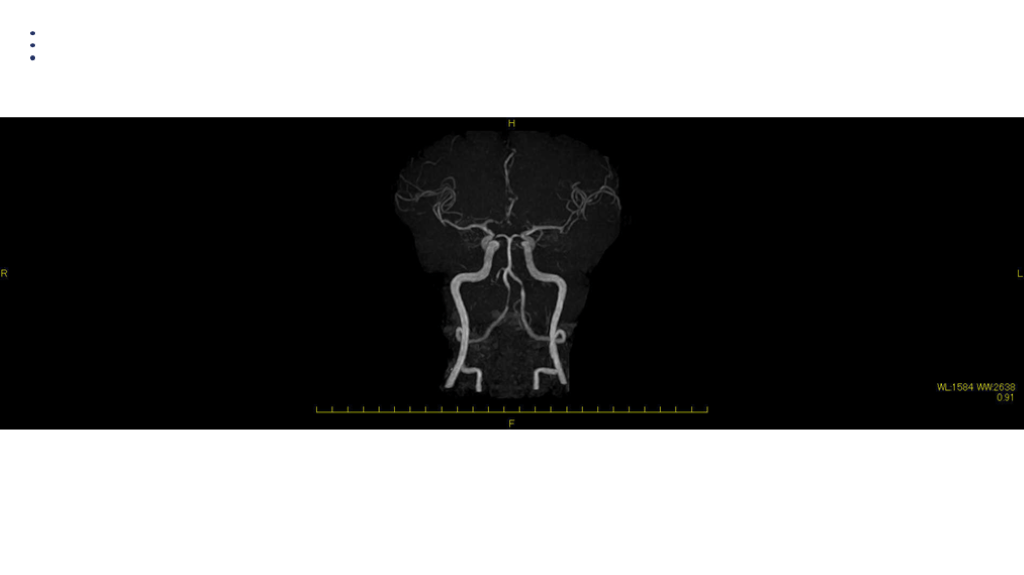

#37.

画像 所見 DAY 14 MRA 悪化